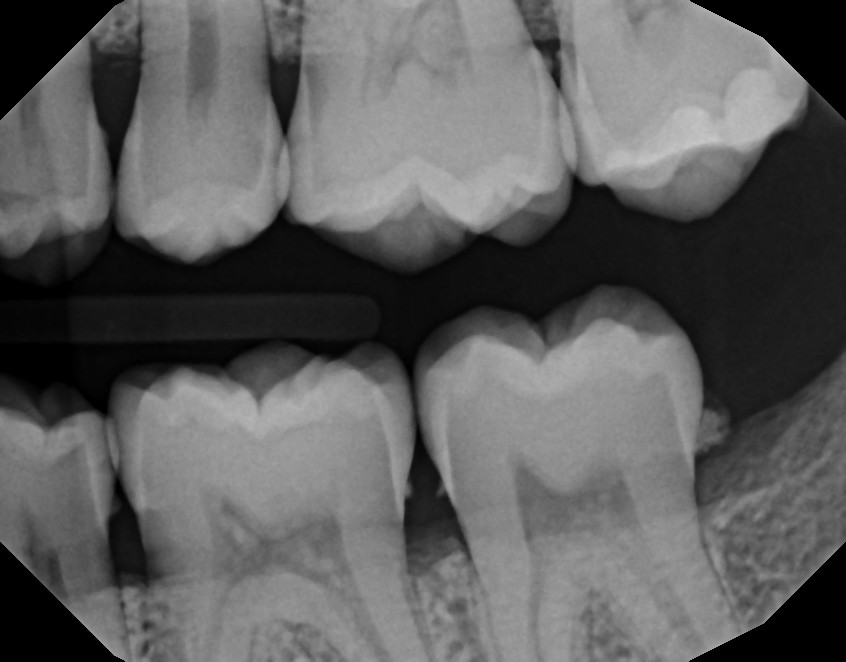

Treatment begins with an exam. The dentist or hygienist measures the spaces between the gums and teeth and looks for signs of inflammation. X-rays may be used to check bone levels.